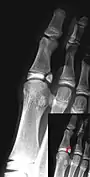

Salter–Harris II fracture of ring finger proximal phalanx.